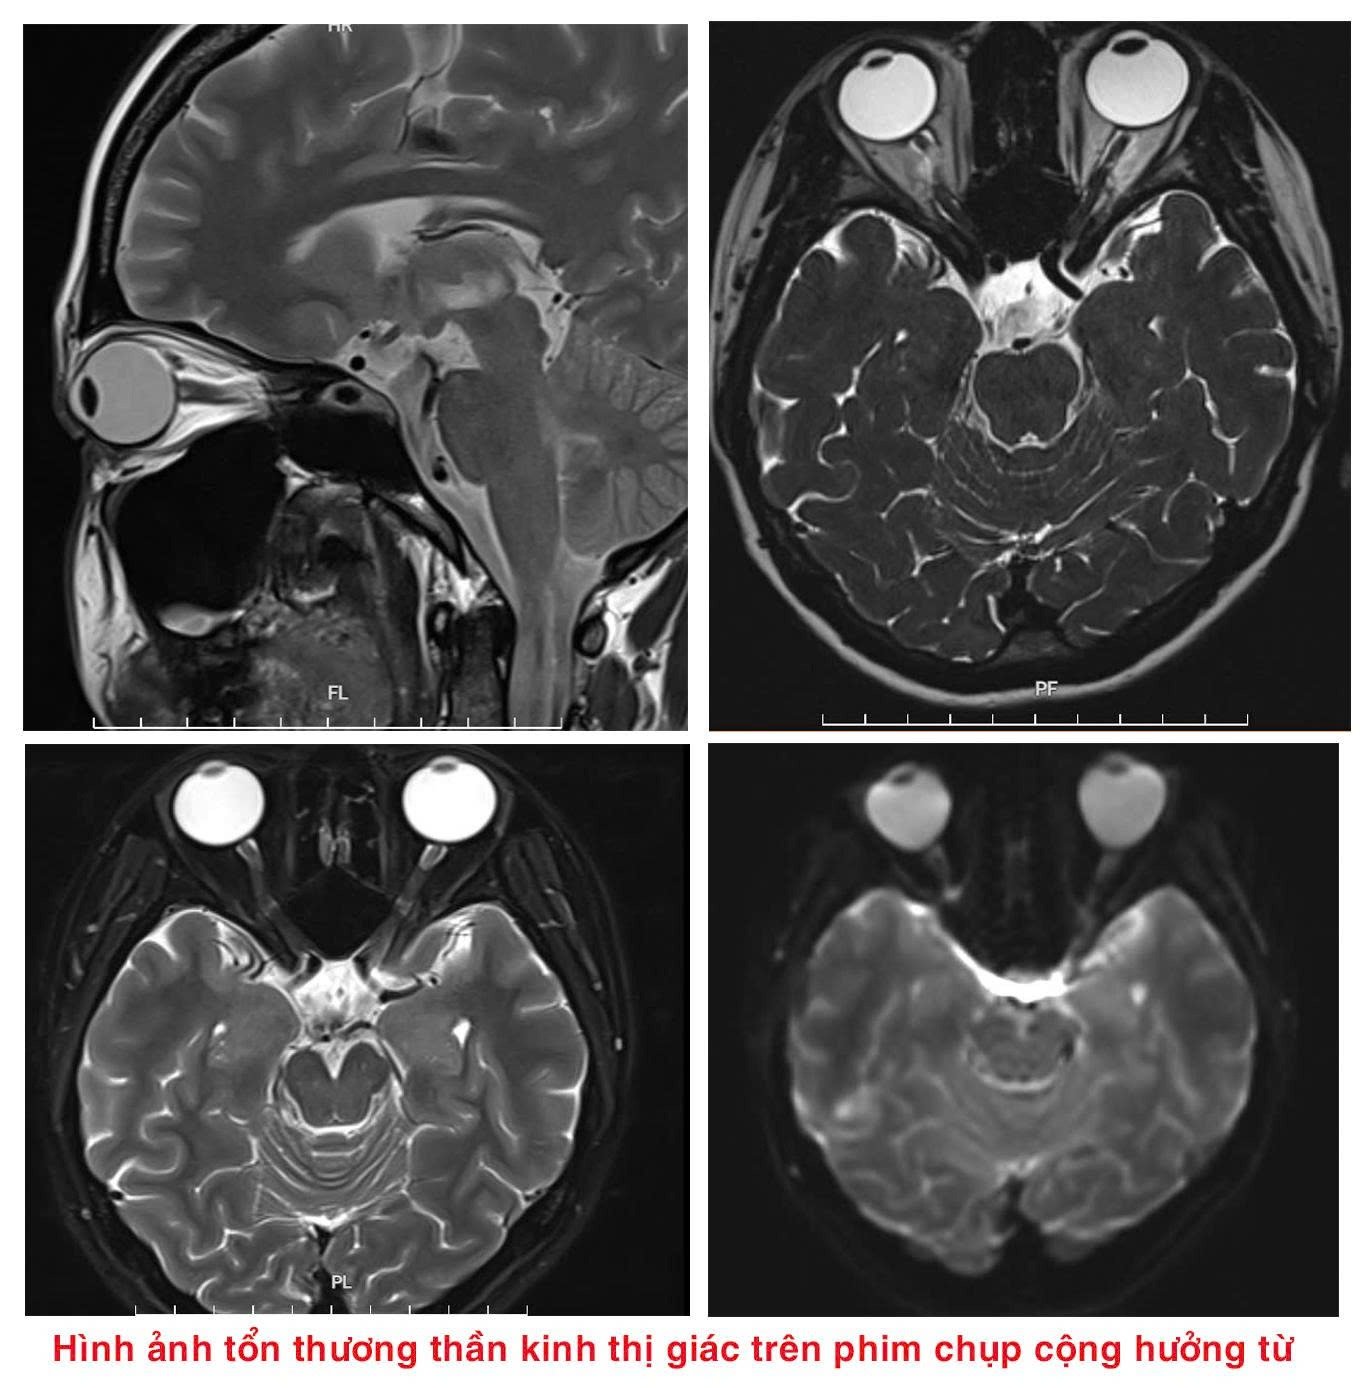

Tại đây, người bệnh được các bác sĩ thăm khám, làm xét nghiệm máu, chọc dịch não tuỷ, chụp cộng hưởng từ sọ não,… Sau hội chẩn lâm sàng, người bệnh được kết luận bị rối loạn Phổ viêm tuỷ thị thần kinh thể tổn thương thần kinh thị, sàn não thất IV, hành tuỷ lưng bên.

Triệu chứng đặc trưng của rối loạn phổ viêm tủy thị thần kinh là viêm thị thần kinh hoặc viêm tủy. Trong đó, viêm thị thần kinh là viêm dây thần kinh thị giác, gây đau nhức trong mắt, đau tăng khi cử động mắt và thường tiến triển nhanh tới giảm thị lực hoặc mù lòa.